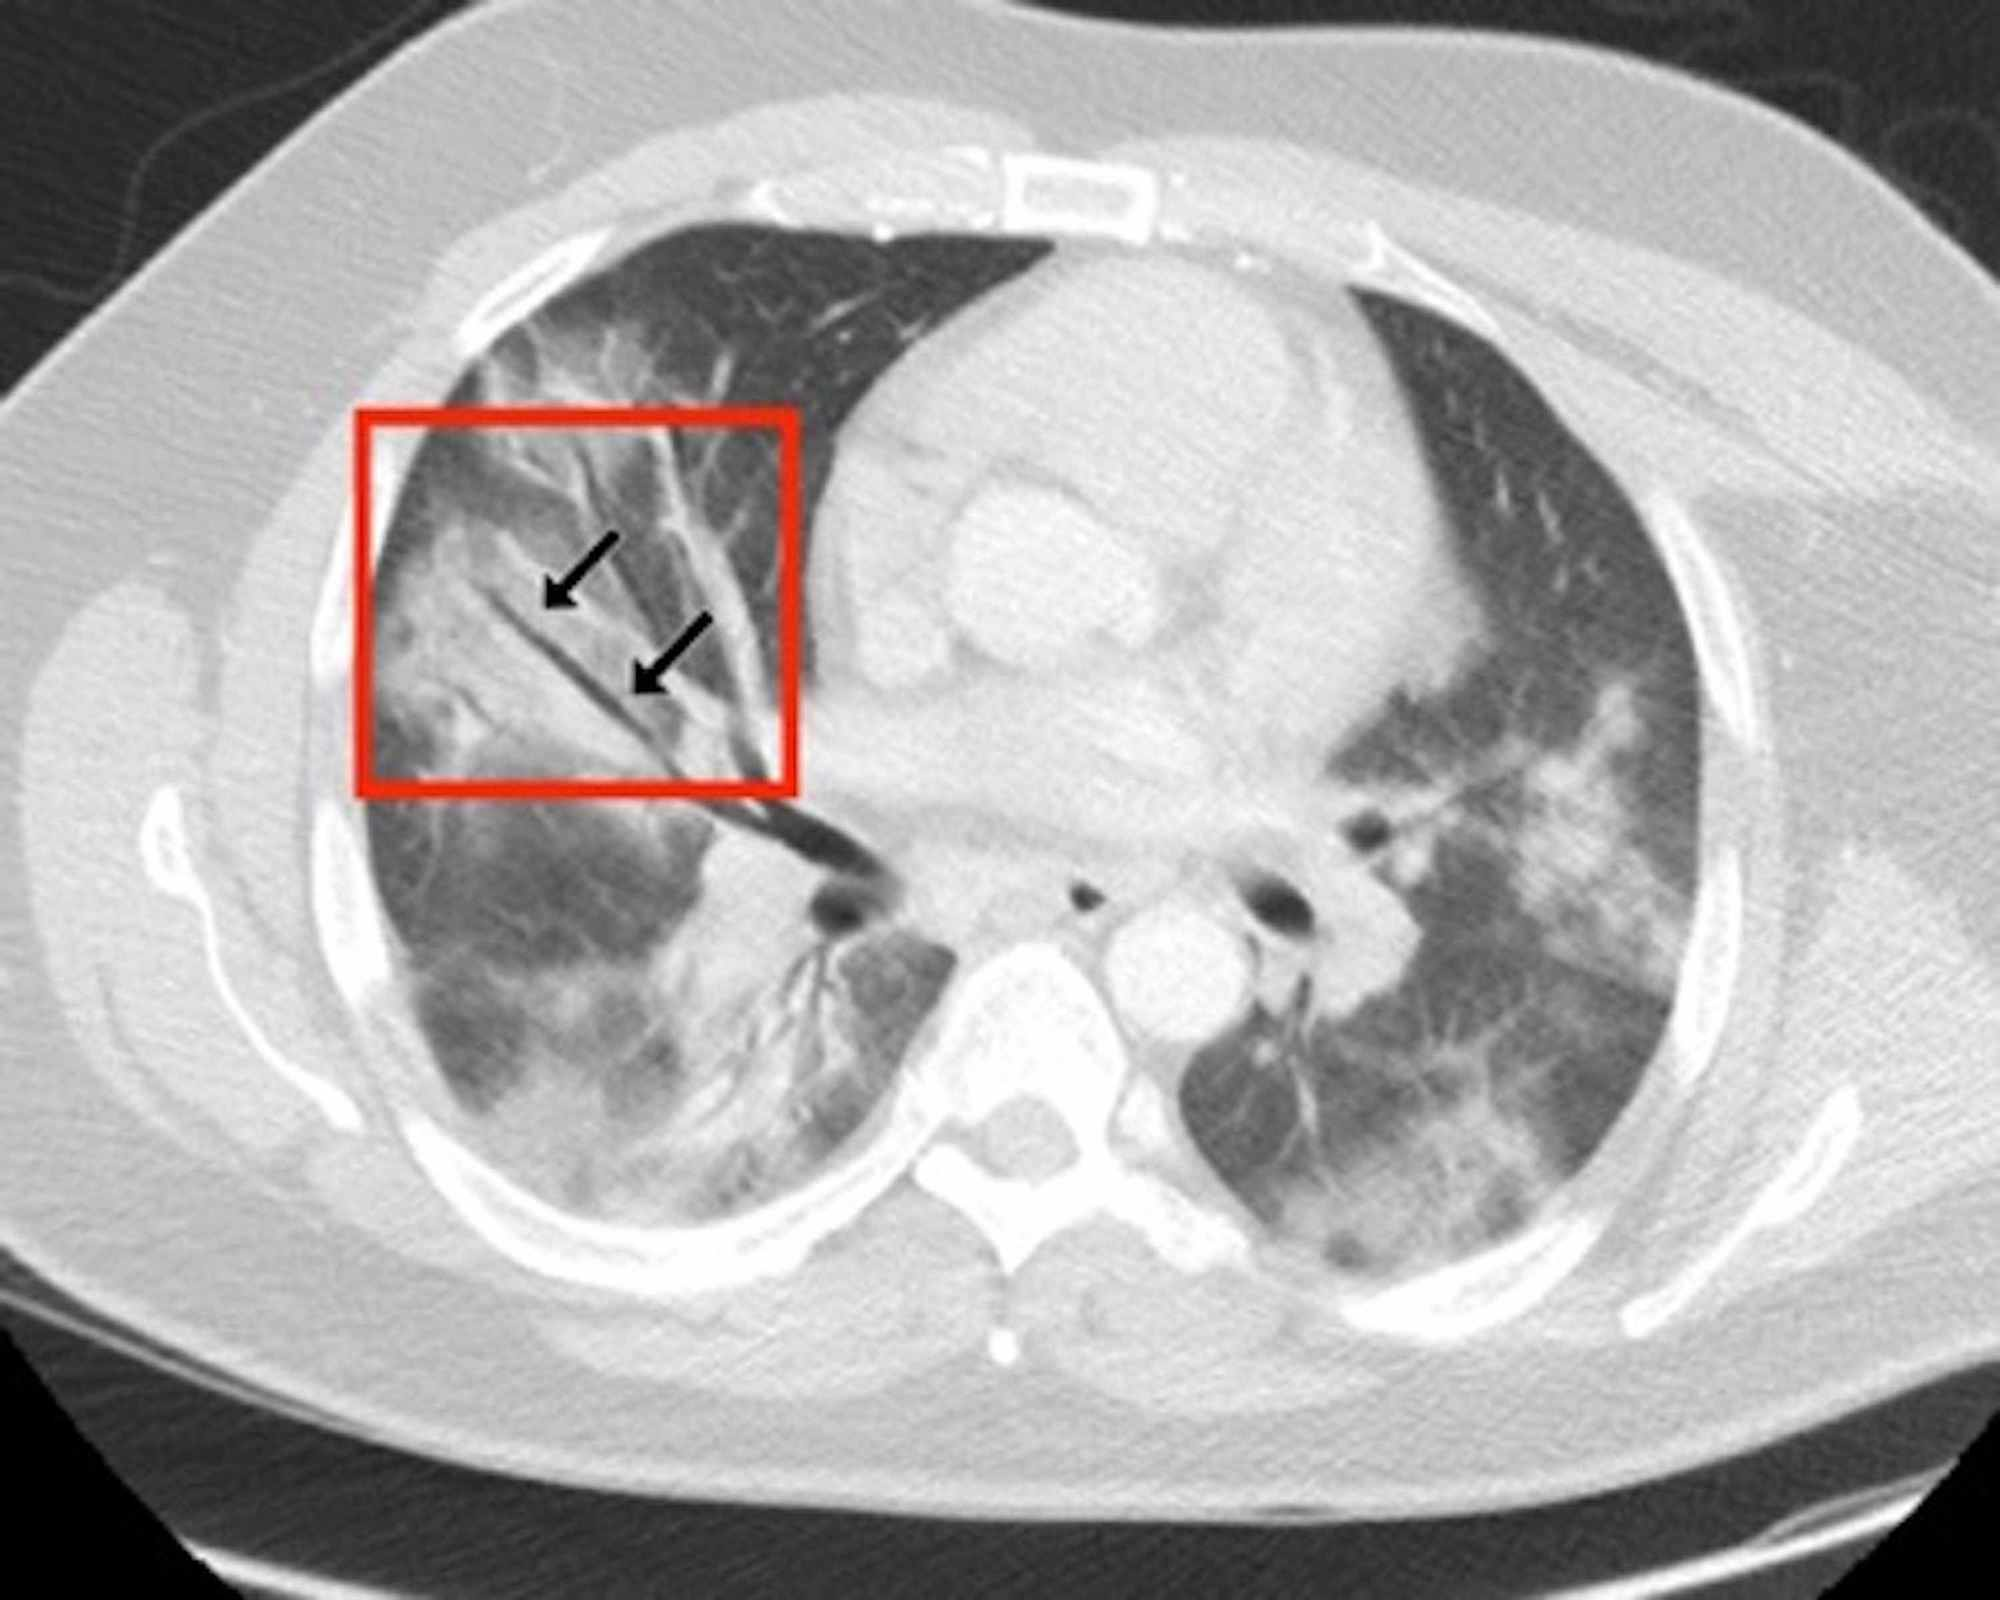

Two board-certified radiologists (E.P. and U.M., with 25 and five years of experience, respectively) reviewed the chest CT images on a picture archiving and communication system (PACS, Carestream Health, Inc, Rochester, NY). Chest CT images were evaluated with both mediastinal (width: 350 HU, level: 40 HU) and lung (width: 1500 HU, level: -500 HU) window level settings. The two radiologists identified pulmonary lesions based on their density, shape, and margin. The locations of the lung lesions were recorded as lobar, axial, anterior, and posterior. Axial locations were categorized as central (inner two-thirds of the lung) or peripheral (outer one-third of the lung). Each lung was divided by an axial line into anterior and posterior halves (Figures 2, 7). The densities of the patchy-confluent lesions were classified as pure GGO, pure consolidation, or mixed. Nodular lesion densities were classified as pure GGO, solid, or partly solid. Margins were classified as well-defined or ill-defined. As most of the lesions were patchy, confluent, and ill-defined margins, lesion sizes were not assessed. Instead, a visual severity score, which was slightly modified from Pan et al., ranging from 0 to 4 for each individual lobes was calculated. Each of the five lung lobes was visually scored on a scale of 0 to 4 as follows: 0: no involvement; 1: less than 25% involvement; 2: 25-50% involvement; 3: 50-75% involvement; and 4: 75-100% involvement.

In the CT images, GGO plus consolidation was observed bilaterally in all 18 (100%) patients. No pure GGO or pure consolidation was encountered in our cohort. The predominant shape was amorphous (72%). Lesions showed no specific lobar predilection, but most lesions were localized posteriorly and peripherally.

The distinctive CT features in our cohort are summarized in Table 3, including GGO and consolidative patchy mostly amorphous (72%) lesions, bilateral posterior and peripheral multi-lobar lung involvement, pleural effusions, subpleural fibrotic lines, subpleural sparing, vascular engorgement, occasional crazy paving, occasional mediastinal lymphadenopathy, pleural thickening, lack of cavitation, and absence of reverse halo (atoll) signs.

Subpleural sparing, which was observed in this patient cohort, has never been reported before, whereas mediastinal lymphadenopathy has been reported occasionally in the literature in English [11]. Focal vascular engorgement, septal thickening, and a subpleural fibrotic line were seen frequently in our cohort, with frequencies of 83%, 72%, and 61%, respectively.

Patients’ CT features are presented in detail in Figures 3, 4, 5, 6, 7, 8. A majority of cases (56%) had moderate severity scores. There was no correlation between the severity score and mortality, p=0.790 (Table 4).